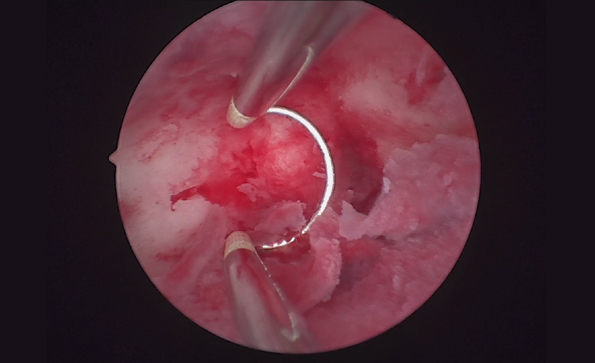

宮腔鏡系統(tǒng)包括哪些設(shè)備?如何消毒?